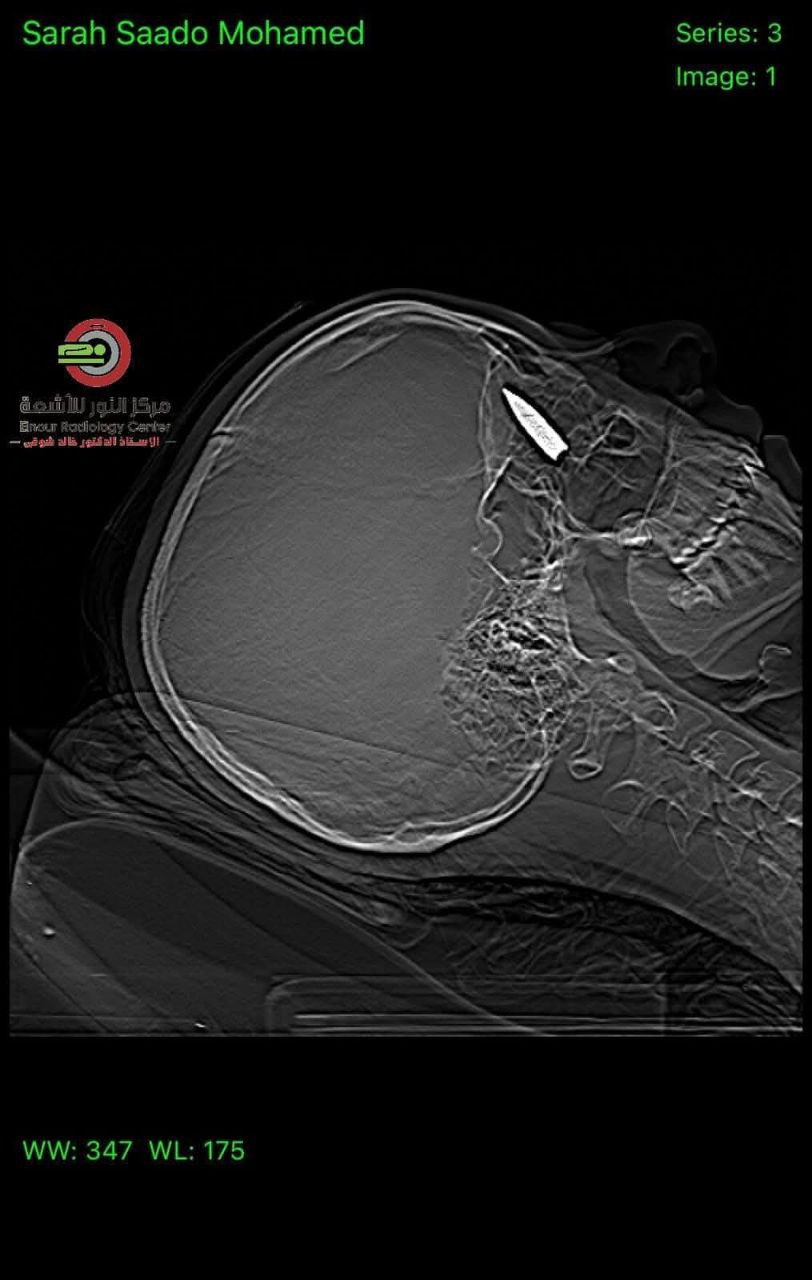

وبحسب المصادر المصرية، تمكن الطبيبان أحمد توفيق ومصطفى عبد الله من إزالة طلق ناري استقر في جمجمة الشابة الفلسطينية، التي خرجت من قطاع غزة لتلقي العلاج في جمهورية مصر العربية.

وكانت الشابة قد أصيبت بطلق ناري اخترق جمجمتها واستقر خلف عينها، إثر استهدافها من طائرة مسيرة من نوع "كواد كابتر"، وذلك خلال نزوحها في منطقة النصيرات.